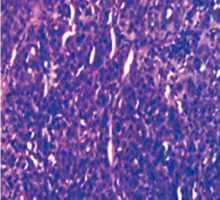

恶性腹膜间皮瘤是原发于腹膜间皮细胞的一种罕见恶性肿瘤,本例恶性腹膜间皮瘤晚期患者,通过特瑞普利单抗联合安罗替尼治疗后,CA125降至正常,病灶评估达到稳定,患者临床获益明显。该治疗方案对提高患者生命质量、稳定病灶起到了一定的作用。

| [5] | Pavlisko EN, Roggli VL. Sarcomatoid peritoneal mesothelioma: clinicopathologic correlation of 13 cases[J]. Am J Surg Pathol, 2015, 39(11): 1568-1575. DOI: 10.1097/PAS.0000000000000495. doi:10.1097/PAS.0000000000000495 |